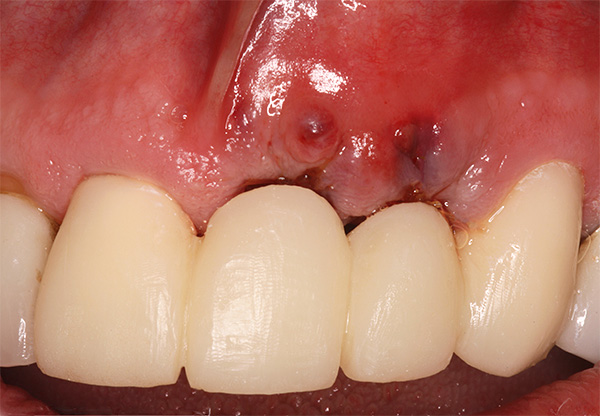

A foto abaixo mostra um exemplo correspondente (a inflamação começou 10 anos após a instalação do implante):

Abaixo, veremos o que pode ser feito para evitar esse resultado adverso.No entanto, antes disso, vamos falar sobre quais sensações são consideradas normais após o implante dentário e quais devem ser consideradas sintomas de peri-implantite, ameaçando evoluir para rejeição do implante.

A foto abaixo mostra um exemplo de inflamação do tecido na área de um implante instalado: